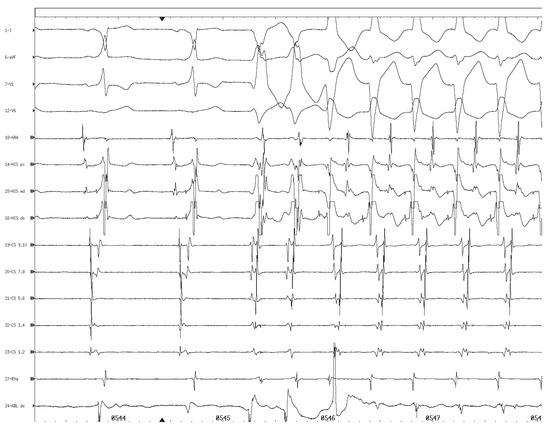

Eigenartiger AV-Block bei Einem Frisch Herztransplantierten Patienten

by Jens Seiler and Michele Martinelli

Cardiovasc. Med. 2005, 8(9), 330; https://doi.org/10.4414/cvm.2005.01123 - 30 Sep 2005

Viewed by 90

Abstract

Fallbeschreibung. Ein 49jähriger Patient wurde wegen terminaler Herzinsuffizienz bei koronarer Herzkrankheit mit Status nach Vorderwandinfarkt orthotop herztransplantiert [...] Full article

Show Figures

Figure 1